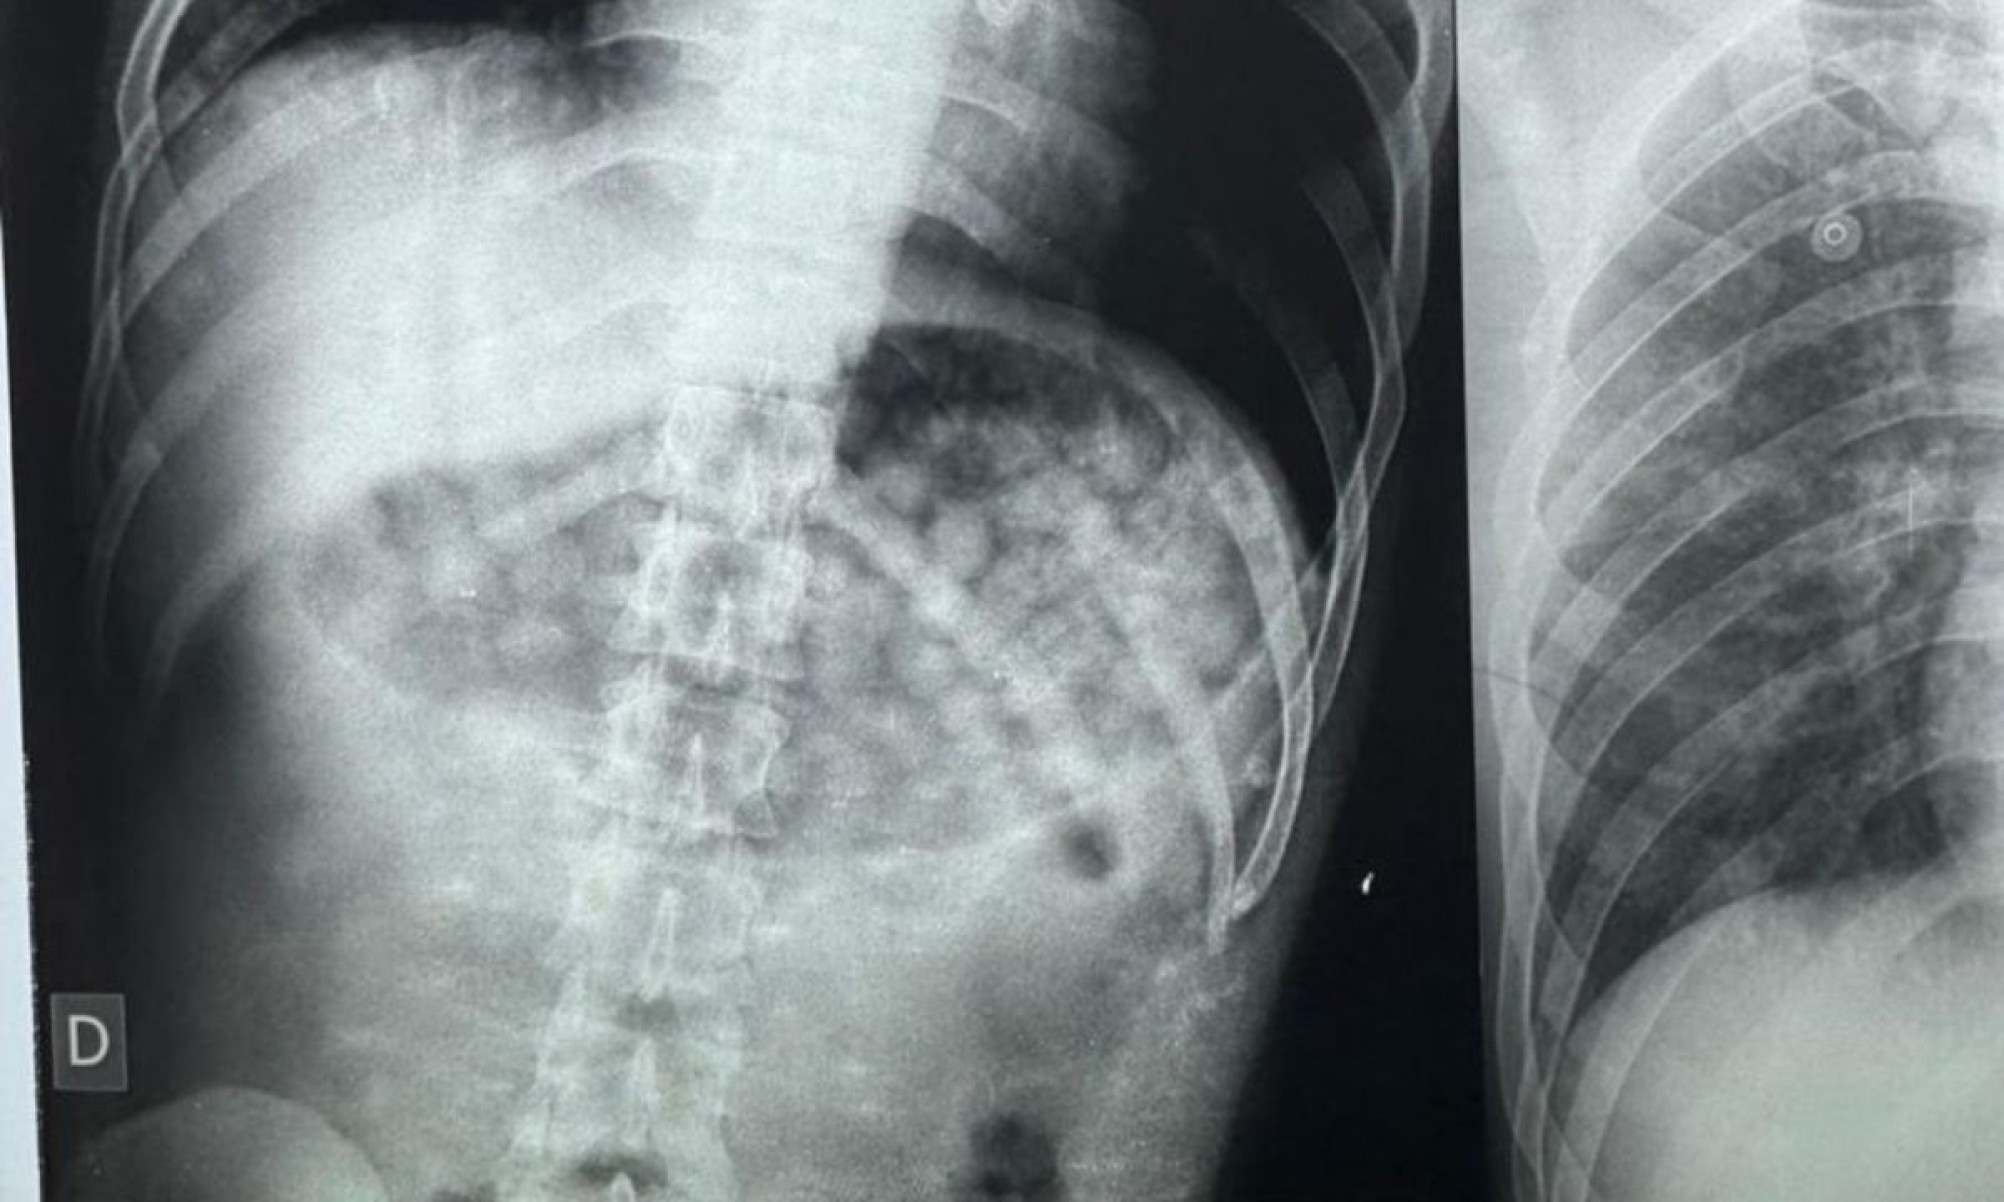

Após receber os primeiros socorros e dar entrada no hospital, foi feito um exame de raio-x que registrou uma grande quantidade de droga no corpo do homem. Segundo a equipe médica, só seria possível determinar a quantidade exata após evacuação ou cirurgia. Momentos depois, ele vomitou mais 61 embalagens com a mesma substância.

Ao todo, 61 embalagens de substância similar a maconha foram expelidas pelo homem